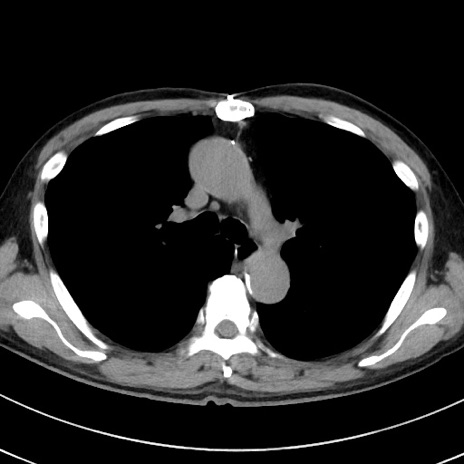

症例38(横断像)

【症例】70歳代 男性

【主訴】腹痛・嘔吐

【現病歴】昨晩より、嘔吐・腹痛あり。今朝になっても嘔吐あり。来院。

【既往歴】心臓バイパス手術、開腹胆摘、腸閉塞

【身体所見】BP 107/71mmHg、HR 116/min、腹部:平坦、軟、下腹部に軽度圧痛あり。反跳痛なし。

【データ】WBC 15100、CRP 0.32